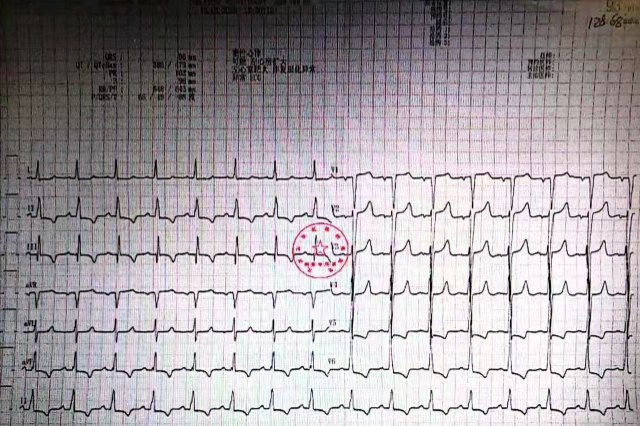

入院时心电图(见图1)